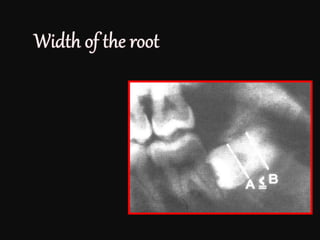

a>b : mesioangular

a=b: vertical

a<b: distoangular